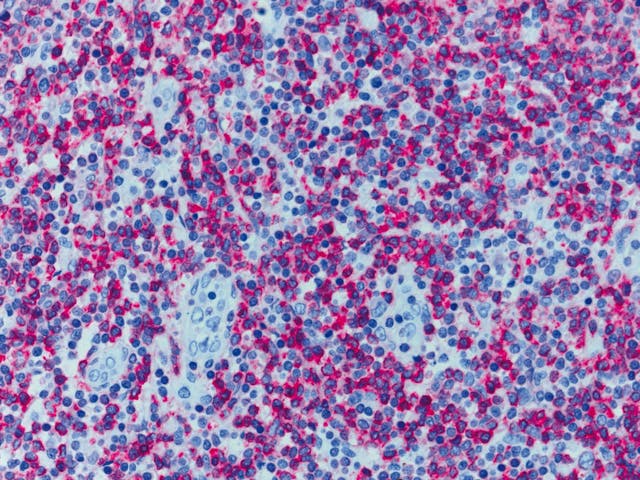

組織學標本(人)

組織學標本(人) 染色體標本(人)